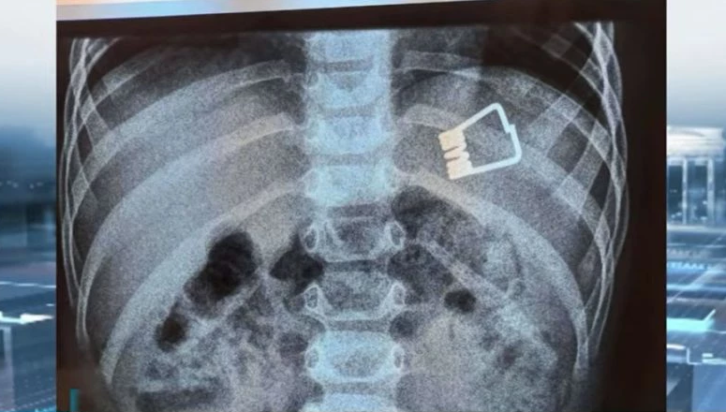

Μια τρομακτική περιπέτεια έζησε ένα μικρό παιδί από τη Λήμνο, το οποίο κατάπιε ένα μανταλάκι και μεταφέρθηκε εσπευσμένα στο Ιπποκράτειο Νοσοκομείο στη Θεσσαλονίκη.

Οι γιατροί κατάφεραν να βγάλουν το ξένο σώμα από το στομάχι του 2χρονου, χωρίς να χρειαστεί να το υποβάλουν σε χειρουργική επέμβαση. Οι γιατροί χρησιμοποίησαν ένα ενδοσκόπιο τελευταίας γενιάς.

Σύμφωνα με όσα μετέδωσε η ΕΡΤ, το παιδί κατάπιε το μανταλάκι στο σπίτι του και αμέσως οι γονείς του το μετέφεραν στο νοσοκομείο της Λήμνου. Το αγοράκι μεταφέρθηκε με Super Puma από στη Θεσσαλονίκη και το Ιπποκράτειο Νοσοκομείο, όπου το ανέλαβαν οι παιδίατροι.